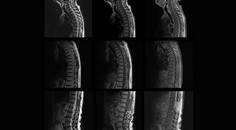

CADASIL Misdiagnosed as Multiple Sclerosis

Anthony Wong, BS; Jacquelyn Johnson, MS, CGCAnthony Wong, BS; Jacquelyn Johnson, MS, CGC - Stroke